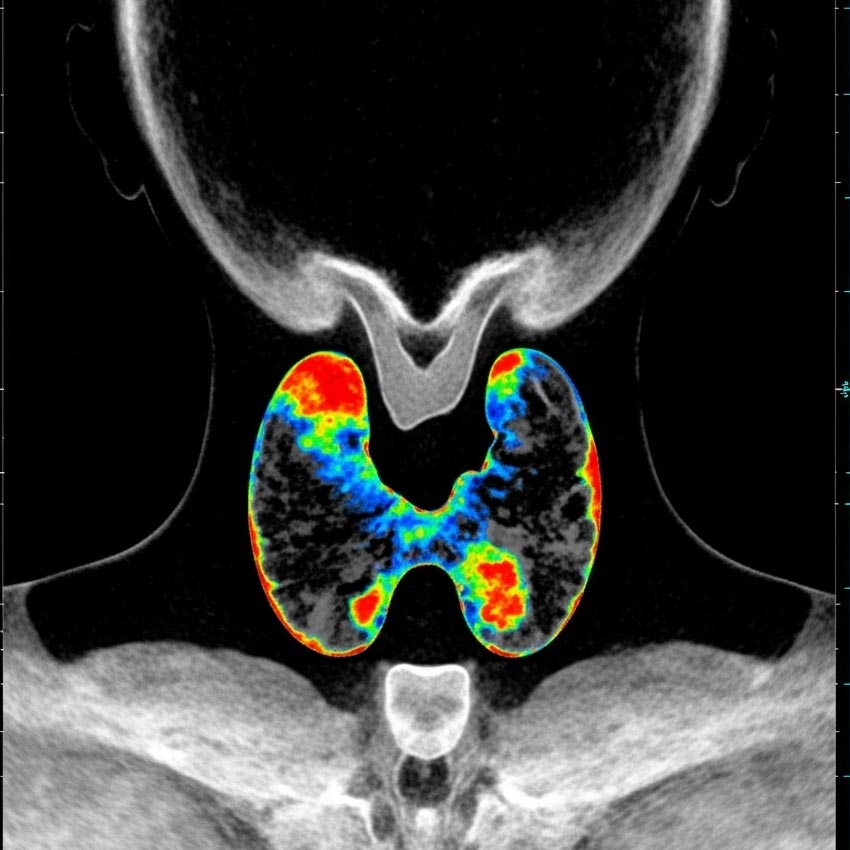

اسکن تیروئید و پاراتیروئید در تهران

اسکن تیروئید و پاراتیروئید در تهران

مواردی که پزشک اسکن تیروئید را تجویز میکند:

1. بررسی علت بزرگی تیروئید (گواتر)

برای تشخیص اینکه گواتر منتشر است یا ندولار، و بررسی عملکرد نواحی مختلف غده.

2. بررسی ندولها یا تودههای تیروئید

برای تشخیص اینکه یک ندول "گرم" (فعال) است یا "سرد" (غیرفعال)؛ ندولهای سرد ممکن است نیاز به بررسی بیشتر داشته باشند.

3. ارزیابی پرکاری تیروئید (هیپرتیروئیدیسم)

برای شناسایی علت پرکاری؛ مثلاً بیماری گریوز یا آدنوم سمی.